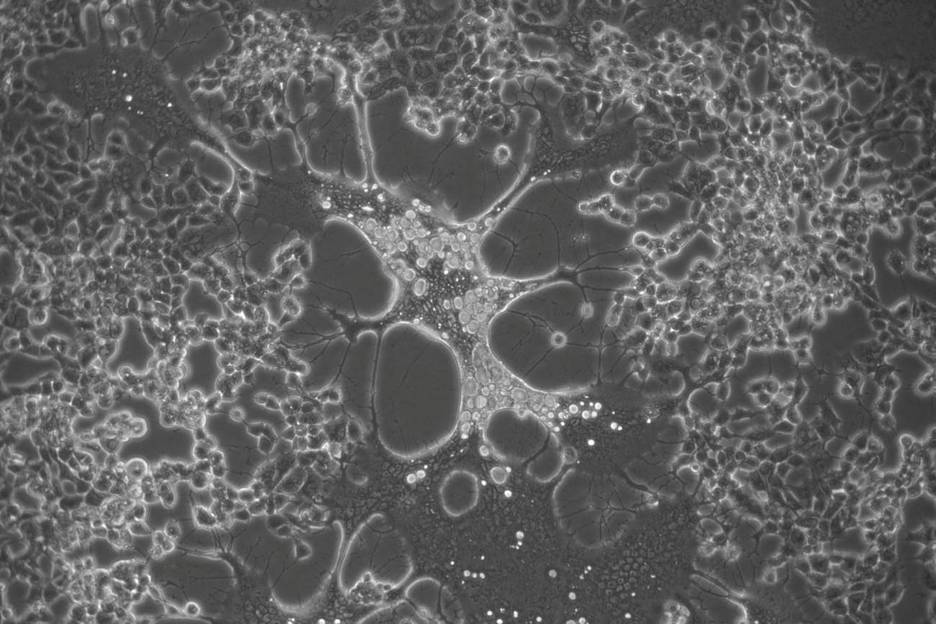

“El virus del herpes simple es uno de los patógenos humanos más prevalentes a escala mundial, para el cual no existe cura o vacuna. Hemos encontrado que ambos tipos de herpes simplex acumulan cambios cuando replican en cultivo celular, lo que puede cambiar su fenotipo muy rápidamente”, explica Antonio Alcamí, del Centro de Biología Molecular Severo Ochoa (CBM-CSIC-UAM), centro mixto del CSIC y la Universidad Autónoma de Madrid.

“Hemos optimizado un método que permite detectar mutaciones nuevas que aparecen con muy baja frecuencia en la población viral cuando estos virus replican. Gracias a ello, observamos cómo el virus del herpes simplex tipo 2 genera muchas más mutaciones al replicar que su homólogo labial (tipo 1), lo que se traduce en una tasa evolutiva más rápida para el primero”, concluye Alberto Domingo López Muñoz, del Instituto Americano de Alergias y Enfermedades Infecciosas.